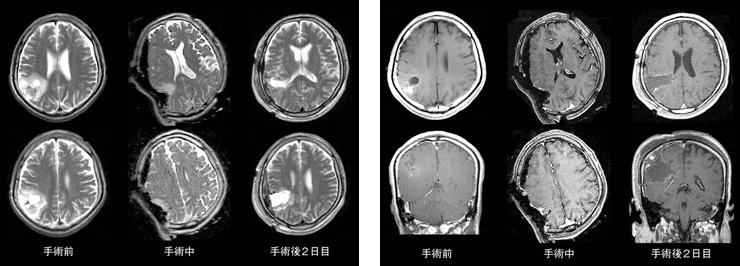

症例:乏突起膠腫のT2強調像(左)と造影T1強調像(右)

T2強調像では,術中MRIにて摘出腔の前方に腫瘍がわずかに残存している。この後,追加切除を行い,手術後2日目の画像では腫瘍がきれいに摘出されていることがわかる。